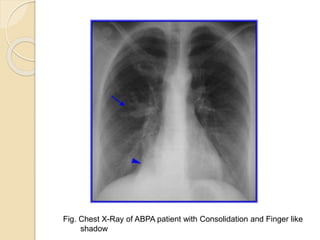

Radiologic Investigations

 Chest radiographic findings

 Transient changes

◦ Patchy areas of consolidation

◦ Radiologic infiltrates: toothpaste and gloved finger

shadows due to mucoid impaction in dilated bronchi

◦ Collapse: lobar or segmental

◦ Perihilar infiltrates may simulate adenopathy

 Permanent changes

◦ Parallel-line shadows representing bronchial widening

◦ Ring-shadows 1–2 cm in diameter representing dilated

bronchi en face

◦ Pulmonary fibrosis: fibrotic scarred upper lobes with

cavitation

CHEST 2009; 135:805–826

Fig. Chest X-Ray of ABPA patient with Consolidation and Finger like

shadow